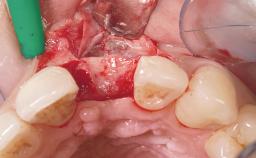

Immediate Flapless Placement of an Implant in a Maxillary Right Lateral Incisor Site

This 43-year-old male patient, a non-smoker, came to our practice because of a fracture of tooth 12 caused by a bicycle accident. Due to the combined para- and infrabony crown and root fracture, tooth extraction, and subsequent implant placement were suggested to the patient as the therapy of choice. The patient had high esthetic expectations with regard to the treatment outcome and asked for an immediate fixed provisional restoration. His individual esthetic risk profile summed up to a medium esthetic risk.